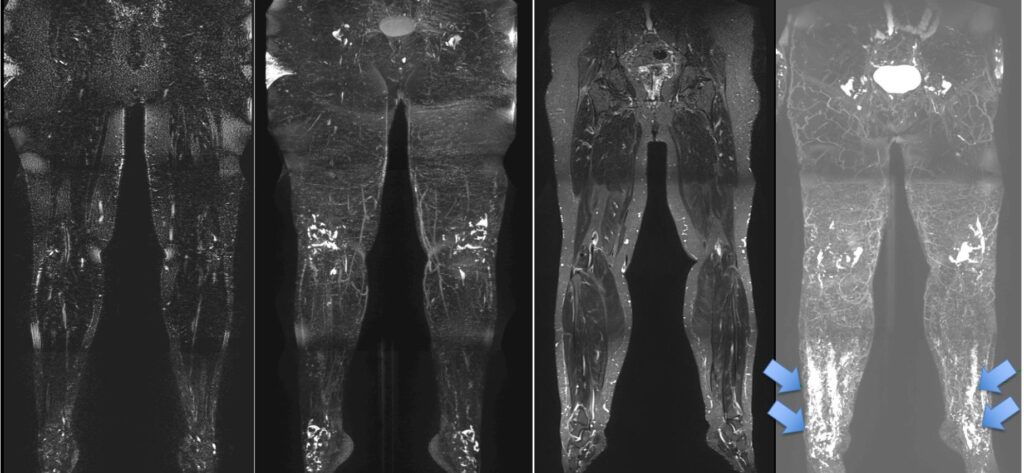

Lipedema

Che cos’è il lipedema? Il lipedema è una patologia cronica caratterizzata da un anomalo accumulo di tessuto adiposo sottocutaneo, prevalentemente a livello degli arti inferiori,